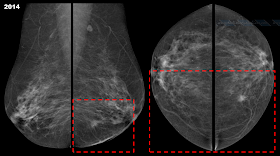

Ιστορικό: Γυναίκα 50 ετών, προσέρχεται για ετήσιο προληπτικό μαστογραφικό έλεγχο (2014).

Ευρήματα: Μαστογραφία: στο έσω ημιμόριο (και σχετικά προς το κάτω) του ΑΡ μαστού ~5 cm από την θηλή παρατηρείται αρχικά μια εστιακή ασυμμετρία υπο την μορφή της ακανόνιστης / ασύμμετρης ακτινοσκιερότητας (~1,20 cm) με υποψία ακτινωτών προσεκβολών και διαταραχή της αρχιτεκτονικής. Στην σύγκριση με την προσκομισθείσα προηγούμενη μαστογραφία (2013) που πραγματοποιήθηκε προ έτους, διαπιστώνεται ότι ως εστιακή ασυμμετρία το εύρημα προϋπήρχε (δείτε συγκριτικά τα εσω ημιμόρια των μαστών στις CC λήψεις) όπως και μια ανεπαίσθητη διαταραχή της αρχιτεκτoνικής (η μαστογραφία είχε σημανθεί με BI-RADS 2 πιθανότατα λόγω του ενδομαστικού λεμφαδένα στο ουραίο τμήμα του ΑΡ μαστού) ωστόσο στην παρούσα μαστογραφία το εύρημα απεικονίζεται εντονότερα και σαφέστερα (και στις δυο λήψεις πλέον). Ο μαστογραφικός έλεγχος προ έτους είχε συμπληρωθεί και από υπερηχογράφημα (BI-RADS 1). Υπερηχοτομογράφημα: στην συμπληρωματική εξέταση που πραγματοποιήθηκε, στην 8η ώρα του ΑΡ μαστού (~4 cm από την θηλή) παρατηρείται υποηχοϊκό (υποψία εσωτερικών υπερηχωγενών ηχοανακλάσεων) ακανόνιστο / ασύμμετρο μόρφωμα (~1 cm) με γωνιώσεις του περιγράμματος / προσεκβολές, οπίσθια ακουστική σκιά και διαταραχή της τοπικής αρχιτεκτονικής, άνευ αιμάτωσης: μαστογραφικό BI-RADS:0 (παρά τις ισχυρές ενδείξεις για πιθανή κακοήθεια[4]) και υπερηχογραφικό BI-RADS: 5. Υπερηχογραφικά δεν εντοπίστηκαν ύποπτοι διηθημένοι λεμφαδένες (ο ενδομαστικός ΑΡ με καλοήθη χαρακτηριστικά).

Διάγνωση: Διηθητικό λοβιακό καρκίνωμα (το ιστολογικό αποτέλεσμα μετά την ολική μαστεκτομή).